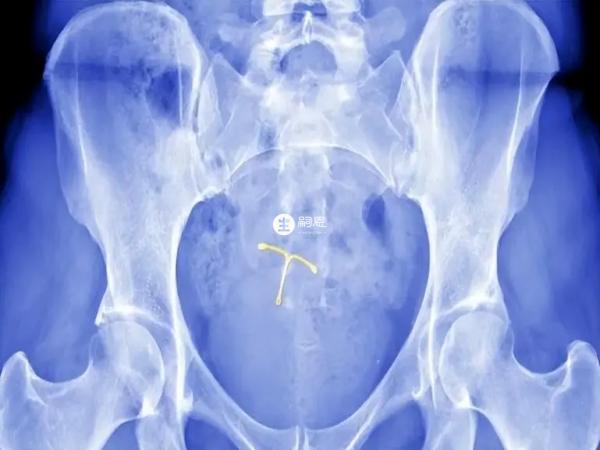

上环也就是指通过手术在女性子宫内放置节育器,通过阻止精子与卵子结合或防止受精卵着床的方式阻断怀孕的途径,从而达到避孕效果,上环作为避孕措施虽安全、有效,但是仍有部分女性上环后出现月经异常、腰酸、腹坠、带环怀孕及异位妊娠情况,也有节育环异位、脱落情况发生可能性,建议咨询专业医生,听取建议了解自身是否适合上环避孕。

上环的好处是能够有效达到避孕效果,上环的时间可长达3-5年,甚至5-8年,如果女性上环后想要自己继续怀孕,也可以选择取环等待1-2个月就可以准备怀孕了,另外女性在上环后要进行定期的检查,这样才可以了解宫内节育器是否有移位等情况。

并非所有女性都可上环,上环的禁忌证主要有怀孕者、各种妇科炎症者、生殖器肿瘤、子宫畸形、宫颈过松、重度陈旧性宫颈裂伤或子宫脱垂者、严重的全身疾患者,上环前需要做妇科检查、血常规检查、白带常规检查及B超检查等,综合考量患者的身体状况。